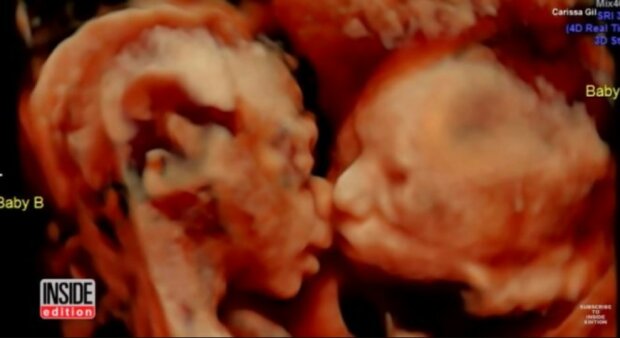

Rodiče nevěřili tomu, co viděli

Carissa Rill šla na 4D ultrazvukové vyšetření. Byla v čtyřiadvacátém týdnu těhotenství. Když se podívala na obrazovku, uviděla dvojčata, která však byla v poněkud podivné poloze. Když se rodiče podívali lépe, zjistili, že se ti malí v matčině břiše líbají! Takový pohled byl pro budoucí rodiče naprosto úžasný! Dokonce i lékař, který měl za sebou přes patnáct tisíc ultrazvukových vyšetření, nemohl uvěřit tomu, co viděl.

Tato fotografie se stala internetovým hitem

Magický okamžik zvěčněný díky ultrazvuku se rychle dostal na internet a získal si obrovskou popularitu. Vůbec nás to nepřekvapuje! Něco takového se jen tak nevidí. Přesvědčte se sami! JE TO NEUVĚŘITELNÉ!